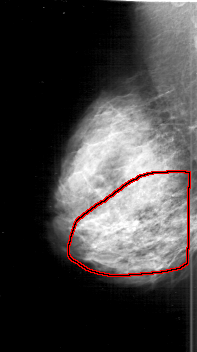

D_4192_1.LEFT_CC

LEFT_CC LINES 5866 PIXELS_PER_LINE 3031 BITS_PER_PIXEL 12 RESOLUTION 43.5 NON_OVERLAY

FILE: D_4192_1.RIGHT_CC.OVERLAY

TOTAL_ABNORMALITIES 1

ABNORMALITY 1

LESION_TYPE CALCIFICATION TYPE AMORPHOUS-PLEOMORPHIC DISTRIBUTION REGIONAL

ASSESSMENT 5

SUBTLETY 5

PATHOLOGY MALIGNANT

TOTAL_OUTLINES 1

BOUNDARY